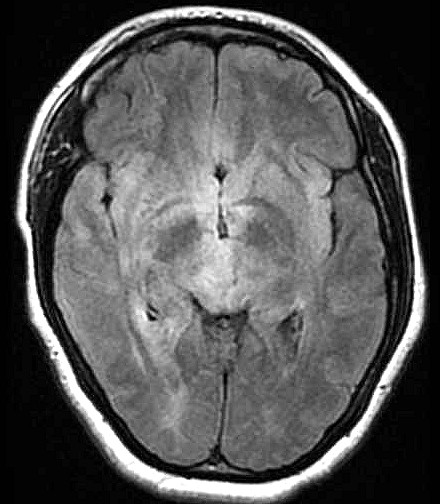

| Fem. 17a. |

| Nódulo sólido homogêneo preenchendo o III ventrículo, com limites precisos, com hipossinal em T1 e hipersinal em T2 e FLAIR, que se impregna por contraste paramagnético. Lesão menor implantada no assoalho do IV ventrículo provavelmente representa disseminação por via liquórica. |

| AXIAIS, FLAIR | T2 | |

| F. 17a. Tumor teratóide rabdóide atípico de III ventrículo. RM | HE | VIM, GFAP | HHF35, desmina, 1A4 | AE1AE3, EMA |